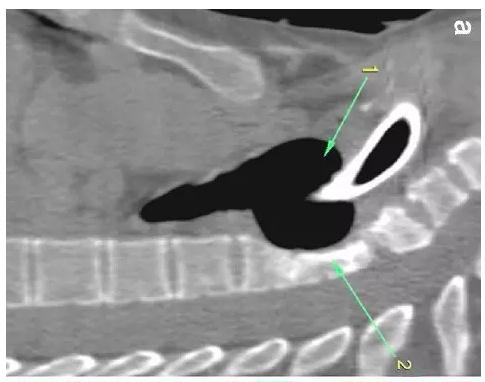

胸部CT顯示氣切套管氣囊周圍氣管擴張,胸1-4椎體前部受到侵蝕(下圖a-c)。

患者入住我院前行胸MRI已經(jīng)發(fā)現(xiàn)類似表現(xiàn)(圖d),當(dāng)時診斷為骨髓炎。

下圖箭頭1為氣切套管氣囊緊貼T1-4椎體水平,造成椎體前部受到侵蝕(箭頭2):